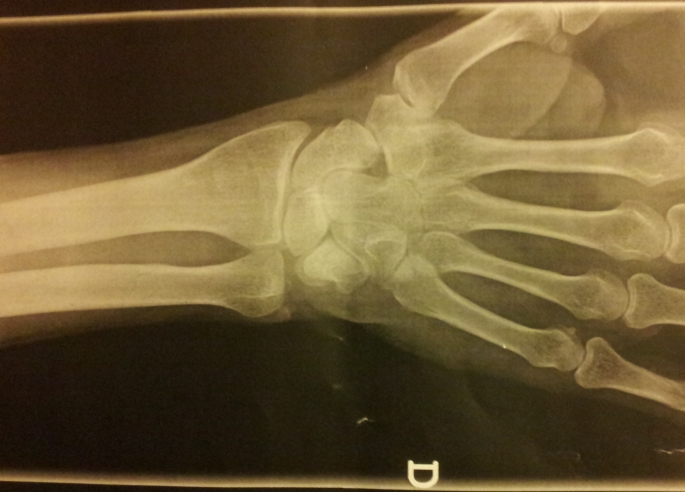

LA FRACTURA FANTASMA

Estoy haciéndome mirar la mano de nuevo, esta vez por la Seguridad Social (glups), porque ha pasado más de un año tras la caída y algo no termina de ir bien.

Así es como me he enterado por mi nueva doctora de que cuando me atendieron en el hospital Sant Pau tuvieron la delicadeza de poner en el informe que soy un borracho y un drogadicto, pero nada sobre mi mano rota o el yeso que me pusieron - total para qué, si ellos sólo se ocupan de urgencias éticas y morales... Antológico.

Por otra parte, el médico de la mutua que me mareó durante tres meses para nada, ahora no acaba de encontrar mi expediente.

- Señor, tiene usted una fractura ilegal que no figura en el sistema. Aunque mira, por lo menos sabemos que es usted yonqui y alcohólico.

WTF.